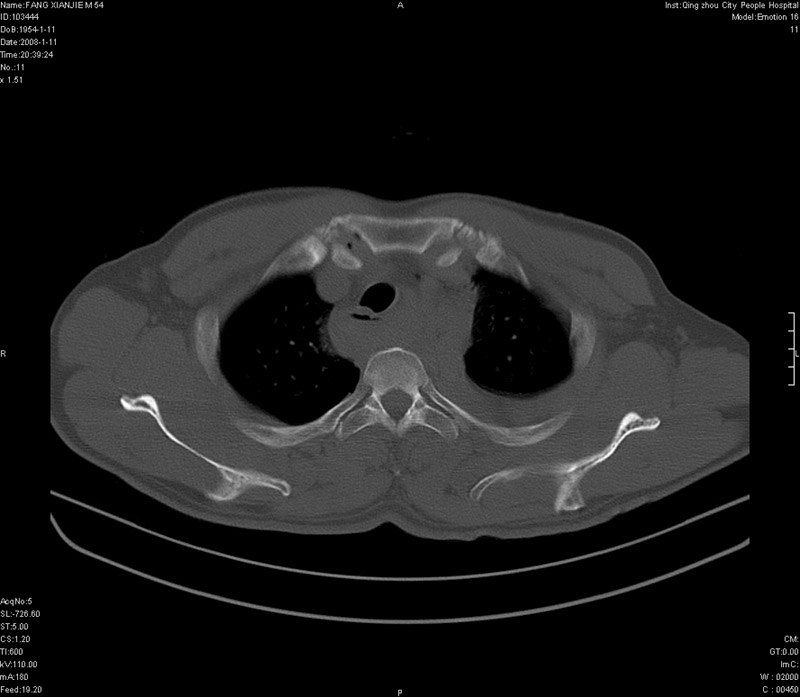

男性,40岁。胸部被车压伤伴胸痛1小时来院就诊。检查:一般情况尚可,血压110/80,胸部及上腹部压痛。结果在三天后公布。骨窗在横断位、冠矢状显示肋骨、胸椎、和胸骨未见骨折征象。

ct11308:胸部外伤1小时(证实病例) (2008-1-13 16:2)结果如下:病人入院后两小时后症状加重,8小时后在征得病人家属同意做了ct增强扫描。如下图。最终临床诊断:外伤性胸主动脉破裂并纵隔内血肿。由于有运动性伪影,胸骨在矢状面重建的图像似有骨折征,这是一种假象,我们称之为“假骨折”,这在多层ct重建中经常性遇到,必要时要结合横断图像鉴别之。现在,病人的一般情况较差,是否要手术家属尚有争议,如果手术修补,难度较大,需要专门预定制作固定支架。

当然,对于该病例,其它非重要的诊断还有:右侧少量气胸;左侧胸腔积液;左侧轻度肺挫裂伤。对于纵隔内血肿,我们曾经遇到过多例,也有怀疑主动脉的破裂,但是,均未得到具体出血部位的明确诊断。